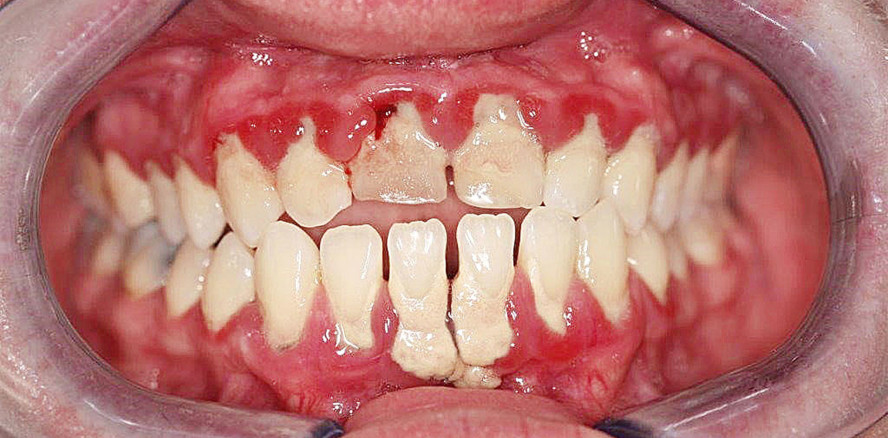

Foto: © Dr. Martin Jaroch, M.Sc., M.Sc.

Über Jahrzehnte wurde Chlorhexidin als Goldstandard in der Parodontitistherapie angesehen. Spätestens seit dem Beginn der sogenannten Full Mouth Disinfection war Chlorhexidin aus dem chirurgischen wie auch dem nichtchirurgischen Bereich nicht wegzudenken. Aktuelle Studien führen dazu, dass die pharmakologische Wirkung dieser Verbindungen immer mehr verstanden werden kann und sich dadurch auch Veränderungen aufzeigen lassen, die keineswegs von den Parodontologen erwünscht sind, wie der folgende Beitrag genauer beschreibt.